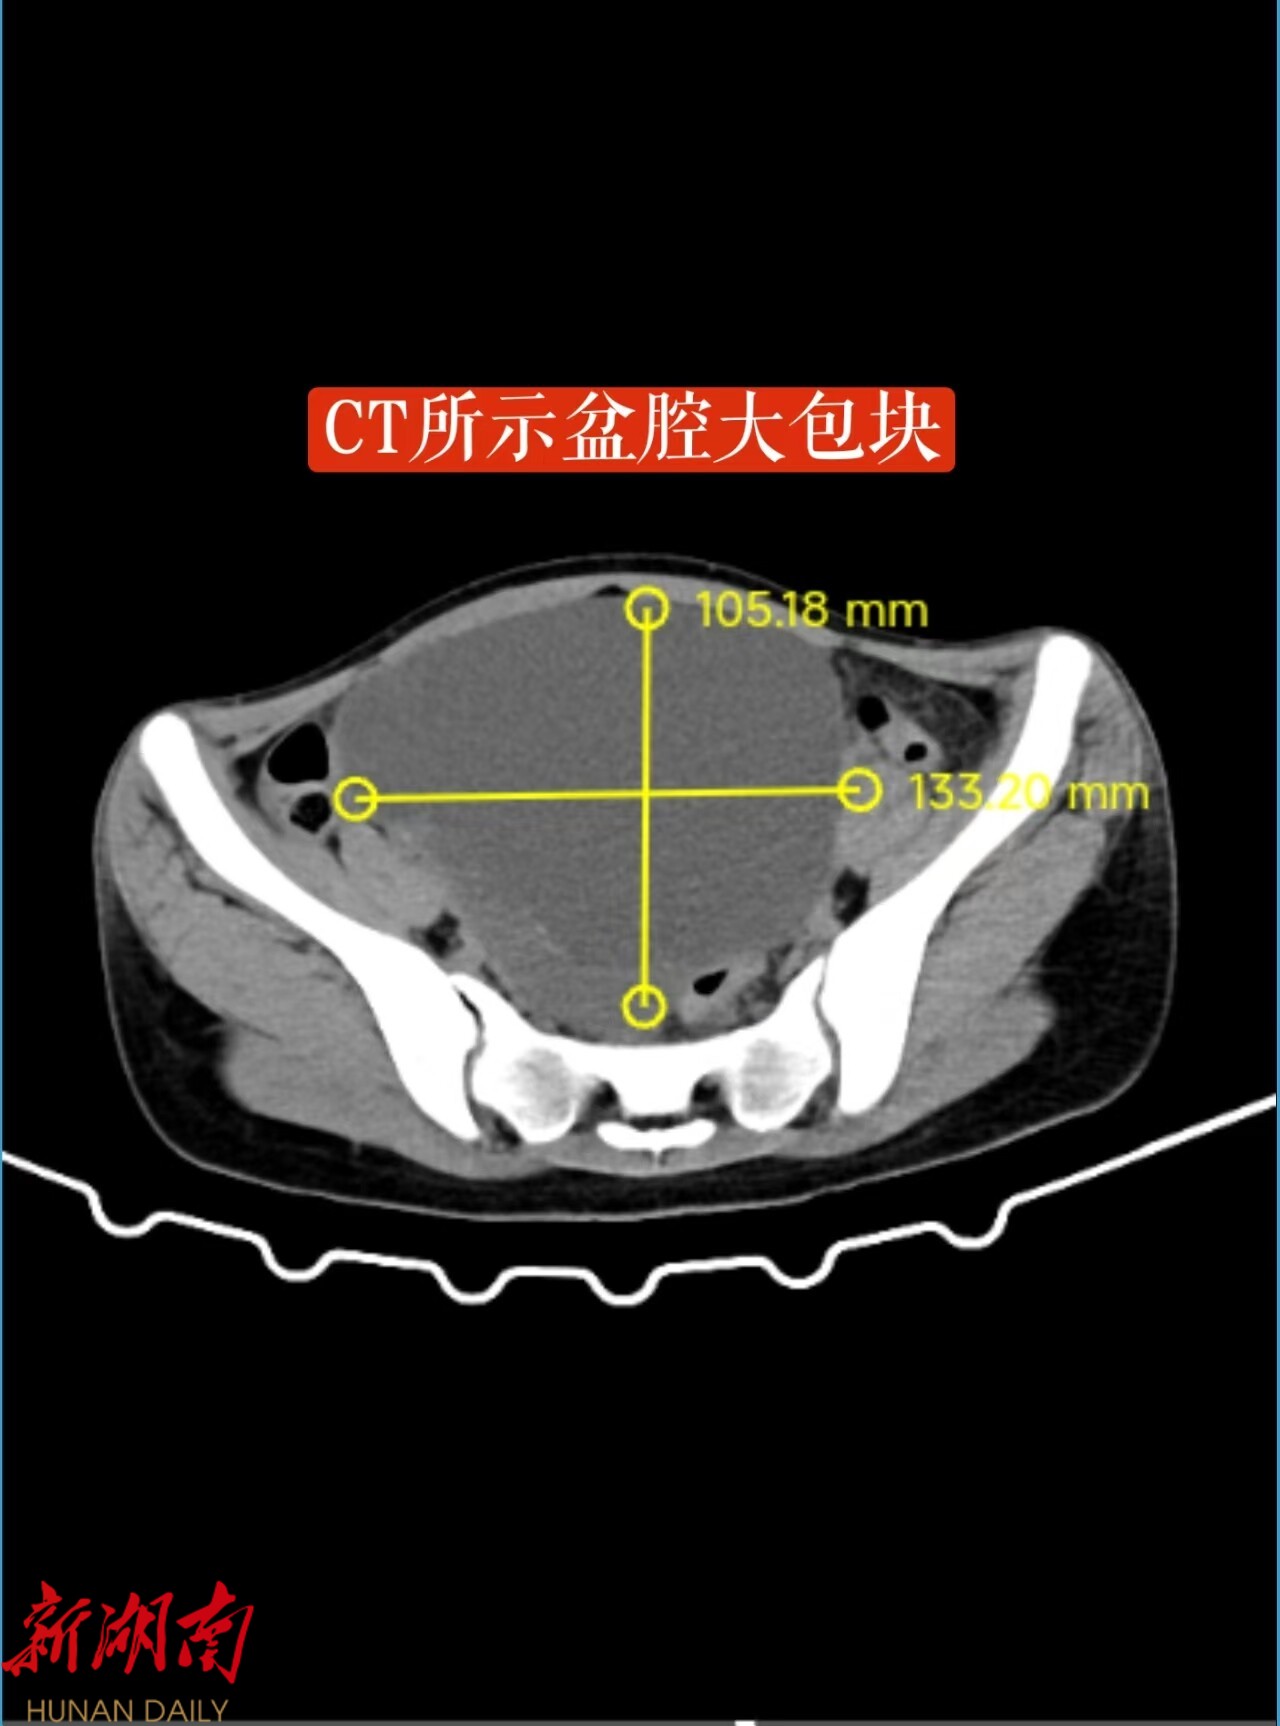

18岁的小婷(化名)是一名热爱跳舞的学生,最近因腹胀到医院检查,发现盆腔内长了一个如“皮球”大小的卵巢囊肿。面对手术,她和家人满怀担忧:手术会不会影响未来的生育?会不会留下疤痕,影响她跳舞时的形象?